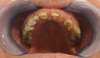

Restaurations par couronnes céramo-céramiques